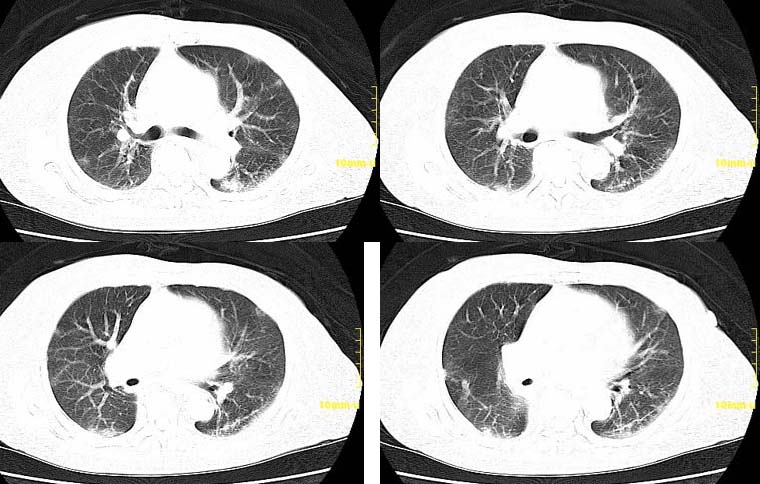

请大家讨论右下肺占位性质。ct值约35-55hu

右下肺癌右肺门淋巴结转移,双肺转移?建议hrct检查。

右下中央型肺癌伴右肺门淋巴结转移、右肺转移。

右下中央型肺癌伴右肺门淋巴结转移、右肺转移

右下中央型肺癌伴右肺门、纵隔淋巴结转移,双肺肺转移